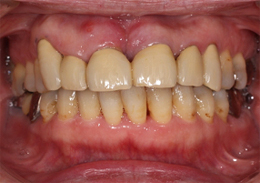

ボーングラフトインプラント(ブロック骨移植をし骨造成をしたインプラント)

ボーングラフトは、十分な量の骨が得られない場合に、骨をブロックで切り出し、移植することで必要な骨を作り出します。

- 主訴

- 上顎前歯の噛む時の痛み

- 治療内容

- 上顎前歯部を抜歯すると大きな骨吸収を予測したため、下顎臼後三角部より骨片を採取し、抜歯時にインプラント埋入と同時に骨造成を行なった

- 治療費用

- 800,000円(税別)

- 治療期間

- 5ヶ月